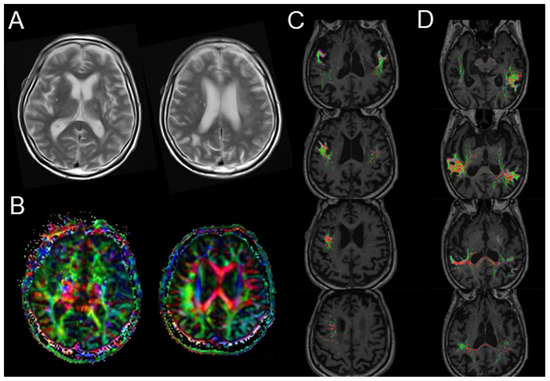

2. Case Presentation